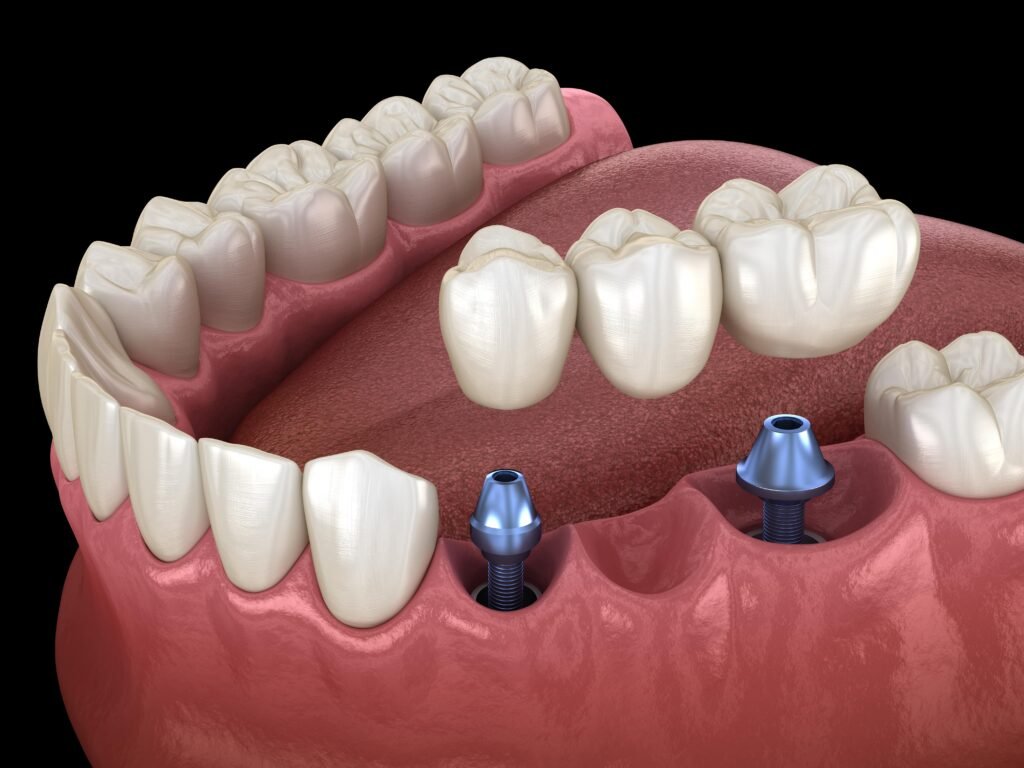

Prosthodontic treatments include crowns, bridges, full and partial dentures, and implant-supported restorations. These solutions are carefully designed to replicate the natural appearance and strength of real teeth while ensuring long-term durability.

- Bridges to replace missing teeth

- Implant-supported prosthetics